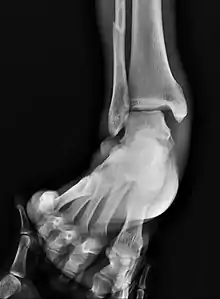

| Fracture of both sides of the ankle with dislocation as seen on anteroposterior X-ray. (1) fibula, (2) tibia, (arrow) medial malleolus, (arrowhead) lateral malleolus | |